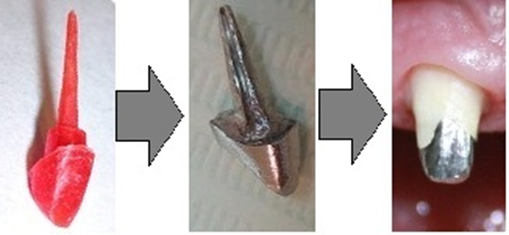

Так выглядит изготовление конструкции. Картинки, просто взял в инете, если что.

Так выглядит после обточки

Этот слепок отливается из гипса, из воска\выжигаемой пластмассы делается будущая вкладка и отдается литейщику. Литейщик отливает её из металла, техник малость обрабатывает, подгоняет и отдает врачу. Врач фиксирует вкладку в зуб с помощью цемента, потом всё это дело обтачивается и покрывается коронкой.

Иногда делают некий промежуточный вариант. Врач моделирует во рту вкладку из выжигаемой пластмассы, а потом отдают эту штуку напрямую в литьё, но как по мне, возни больше, профит сомнительный.